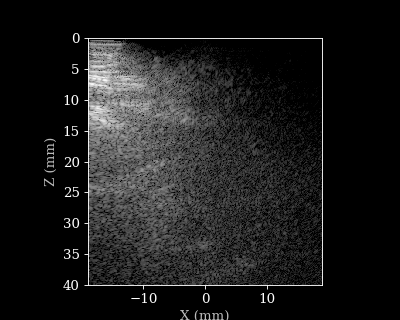

Change transmits on the fly

We now used 11 transmits throughout for every frame. We can also sweep through the the transmits for each frame to see how it affects the image quality.

animate_images(images, "./tx_sweep.gif", scan, interval=100, cmap="gray")

15/15 ━━━━━━━━━━━━━━━━━━━━ 1s 26ms/step

Transmit sweep